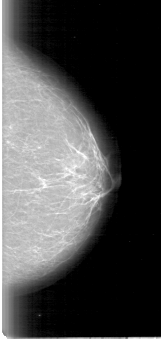

D_4009_1.LEFT_MLO

LEFT_MLO LINES 5386 PIXELS_PER_LINE 2536 BITS_PER_PIXEL 12 RESOLUTION 43.5 NON_OVERLAY